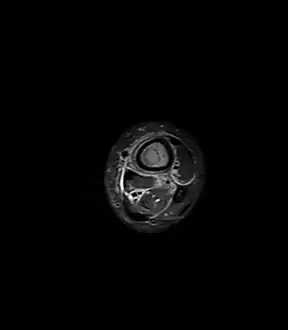

Axial T1-weighted MRI pre-contrast enhancement showing that the intramedullary collection is T1-hyperintense suggesting proteinaceous viscous fluid consistent with infection.

Axial T1-weighted fat-saturated MRI image following IV gadolinium contrast demonstrating the intramedullary lytic area seen on radiography to be ring enhancing consistent with a purulent fluid collection. Extensive circumferential periosteal enhancement is noted. There is also substantial bone marrow enhancement.